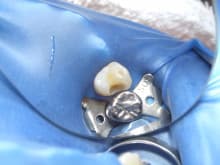

右上小臼歯の虫歯治療

右上小臼歯の虫歯に

ハイブリットセラミックによる

ダイレクトボンディング治療を行った症例についてご紹介します。

治療途中です。

唾液や細菌感染を防ぐため

ラバーをかけて治療を行っています。